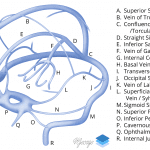

- Multiple areas of segmental thrombus in the nondominant left transverse sinus with occlusive thrombus extending from the transverse-sigmoid sinus junction into the left internal jugular vein

- Lack of opacification of the bilateral cavernous sinuses

- Nonopacified, engorged left superior ophthalmic vein

- Nonocclusive filling defect in the right jugular bulb

- Dural venous and cavernous sinus thrombosis

Dural venous sinus thrombosis with multiple areas of segmental thrombus in the nondominant left transverse sinus and occlusive thrombus extending from the transverse-sigmoid sinus junction into the left internal jugular vein. Lack of opacification of the bilateral cavernous sinuses is concerning for bilateral cavernous sinus thrombosis. There is also thrombosis of the left superior ophthalmic vein and nonocclusive thrombus in the right jugular bulb. No acute hemorrhage or mass effect.